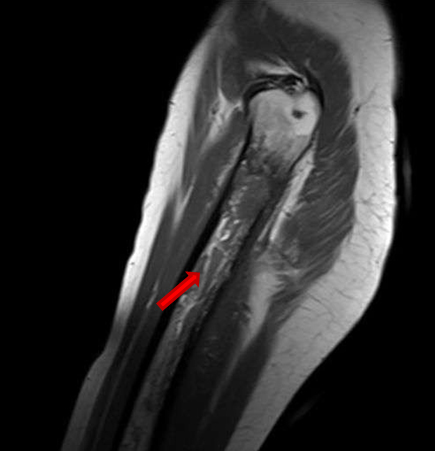

During her hospitalization time, she presented sudden and massive vaginal bleeding that caused hemorrhagic shock requiring Intensive Care Unit admission, strong hemodynamic support, blood transfusions, and uterine right artery embolization. Once recovered, she developed severe pain and inflammation on her left thigh. Femoral magnetic resonance image revealed significant signal alteration of femoral diaphysis, with cortical disruption and muscle edema, suggesting femoral osteomyelitis originated from adjacent infected soft tissues (Figure 9) and (Figure 10).

Figure 9: MR image. Left femoral head avascular necrosis. Left femoral diaphysis severe impairment, affecting around 200 mm, with aheterogeneous morphology, with cortical disruption and moderate edema on adjacent muscles.

Figure 10: MR image. Left femoral head avascular necrosis. Left femoral diaphysis severe impairment, affecting around 200 mm, with aheterogeneous morphology, with cortical disruption and moderate edema on adjacent muscles.